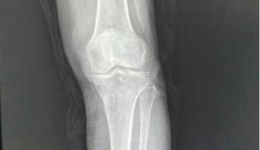

医患故事前段时间,一位28岁的年轻女士一瘸一拐地走进四川省第五人民医院(四川省老年医院)康复医学科门诊。本人描述:自己从台阶跳下来时,右膝关节出现剧烈的疼痛。经医生检查后诊断为前交叉韧带损伤,已行韧带重建术,但还是不能完成下蹲,走路...

“医生,我手术之后可以正常下地行走,可以开始旅游了么?”今年71岁的黄阿姨在手术前充满期待的问道。黄阿姨是一位热爱生活、热爱旅游的人,但是,近2年来,由于膝关节疼痛,不能走远路就只能待在家。两个月前,黄阿姨左膝关节疼痛加重,行走都只...